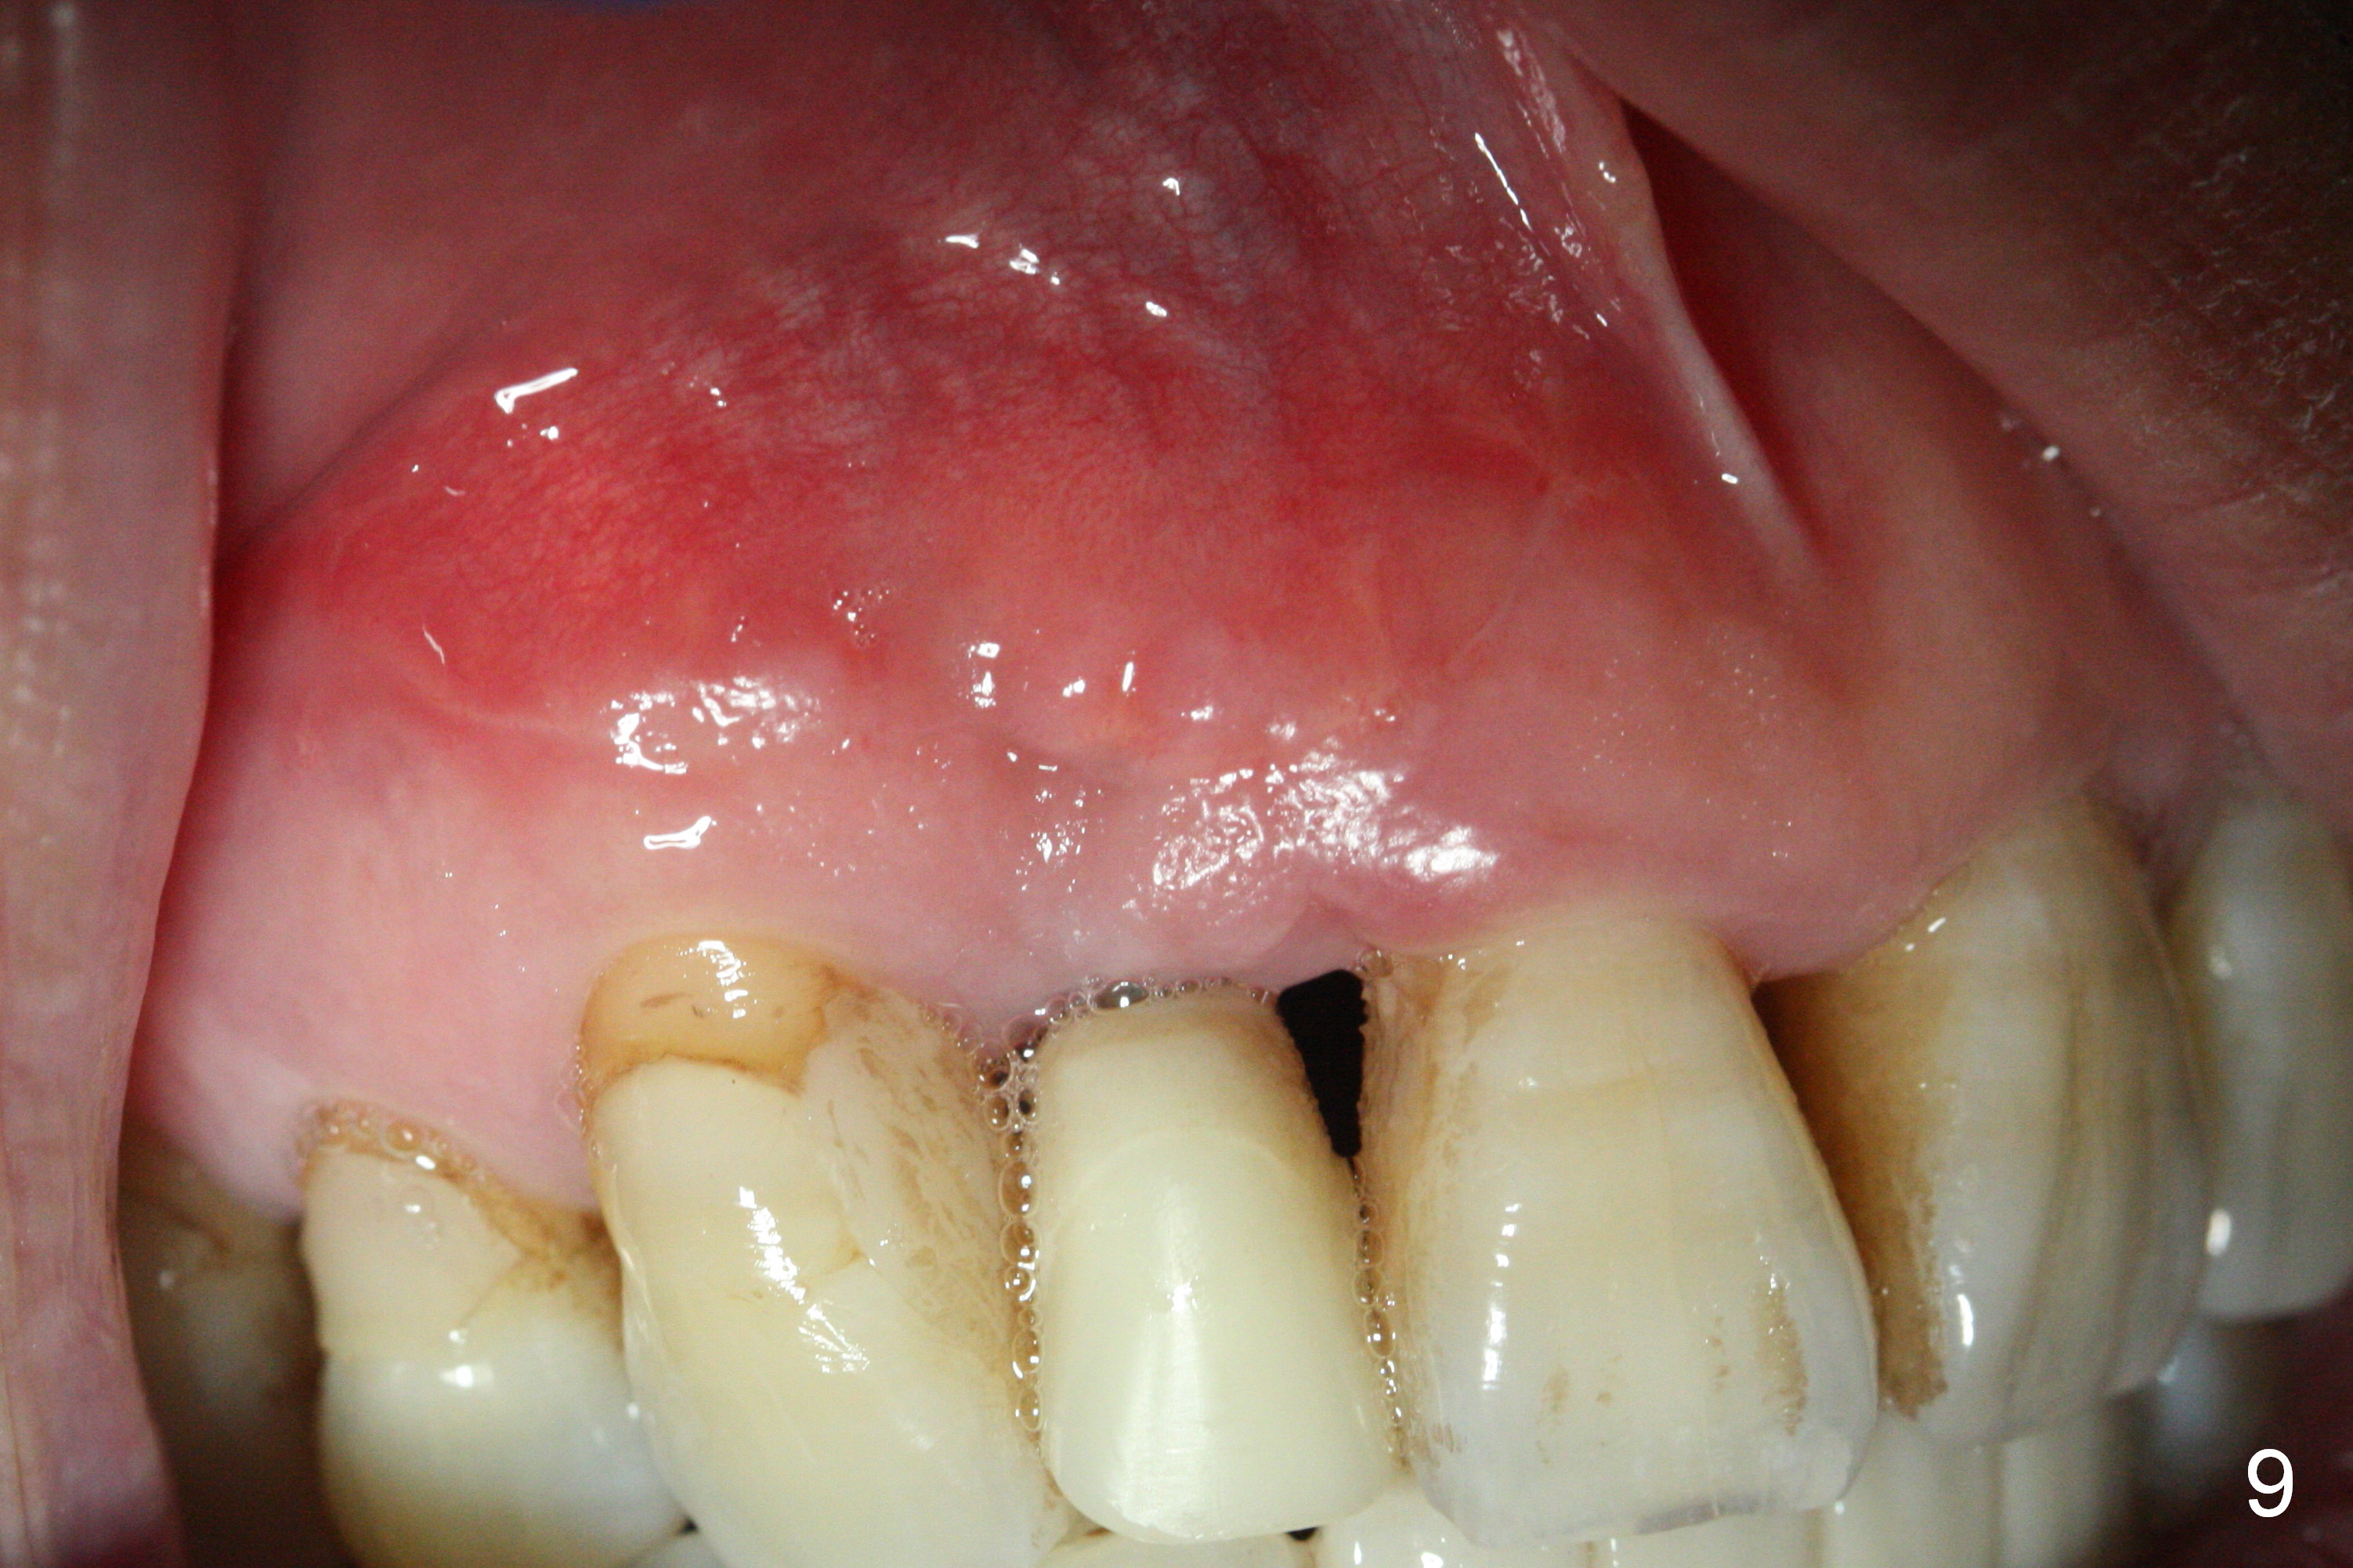

Preop exam shows the apparent wide ridge at #7 (Fig.1). What is ignored preop is the concavity in the apical buccal region (Fig.2 *). When a 3x16(4) mm 1-piece implant is being placed (Fig.3 *, flapless), the apical buccal plate vibration is felt. The biggest mistake is that initial osteotomy is ~ 6 mm shy of the implant length, partially because of 6 mm gingival height. Since the tooth #6 is symptomatic after RCT with paste overfill (Fig.4 >), apicoectomy is contemplated at #6 with exploration of the buccal plate at #7 (Fig.5). Since the implant appears to be long enough, implant apical resection is performed (Fig.6). Since there is coronal thread exposure due to previous periodontitis (Fig.7 <), bone graft is placed in these 3 defective areas after decortication.

Extending the initial osteotomy to the full length of the implant is critical. If perforation is detected early, the trajectory can be changed. Incision should be made if there is no CBCT study. The incision heals 1 and 4 weeks postop (Fig.8,9). The patient returns for final restoration 6 months postop. Apical defects appear to have healed at #6 and 7 (Fig.10,11). Fig.12 is taken 11 months postop and 5 months post cementation. The patient has an accident 9 months post cementation. In fact the implant is alright, while the tooth #6 fractures and #8 subluxates.